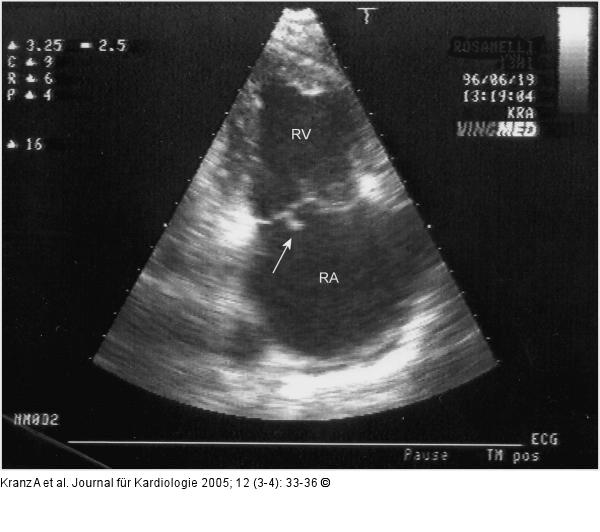

Abbildung 9: Endokarditis - Valv. tricuspidalis

Endokarditis d. Valv. tricuspidalis (TTE) |